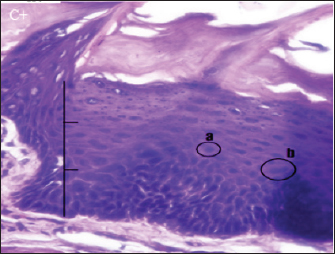

Fig. 2. Histopathologically described the rat tongue epithelium in the negative control group (C-), microscope at ×400. (a) basal layer with a hyperchromatic nucleus and basophilic cytoplasm; (b) spinosum layer with cells of irregular polygonal shape; (c) cells in the granulosum layer with oval cell shape; d. the layer of corneum filled with keratin.

In group (C-), the epithelium of the rat’s tongue had a normal histopathological appearance. There appeared to be a regular epithelial stratification among the cells, with healthy cell turnover in each layer. The base layer consists of hyperchromatic nuclei, while the spinosum layer is composed of irregular polygonal cells. Granulosa has oval-shaped cells. Nucleus and cell organelles vanish, followed by a transition to the corneum layer, demonstrating keratinization development (Fig. 2).

Histopathological examination of the group (C-) revealed no abnormalities in the stratified or basal epithelium. This group did not observe OED because they were not triggered by DMBA. Normal oral epithelium consists of a basal layer of cuboidal or prismatic epithelial cells with hyperchromatic nuclei and basophilic cytoplasm. There are several cells with irregular polygonal shapes in the spinosum layer. The granulosum layer contains oval-shaped cells. The further above granulosum layer, nucleus is lost, and the layer becomes flatter. The outermost layer is the corneum layer, which contains no nucleus and is composed of keratin.